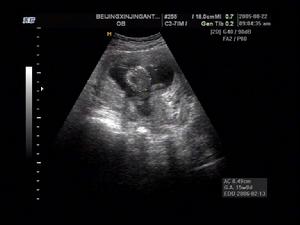

2.CT 和MRI 可行顱內病灶精確定位和放射測定。